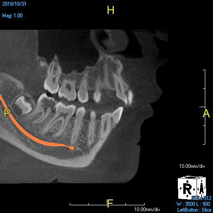

(8.) An original finding of a small lesion on the mesial root of tooth No. 30 was not accompanied by any outward symptoms; therefore, the patient delayed pursuing treatment. When a follow-up CBCT scan was acquired 6 years later, the easy-to-visualize increase in the dimensions of the lesion motivated the patient to elect a treatment plan.

Figure 8

(9.) An original finding of a small lesion on the mesial root of tooth No. 30 was not accompanied by any outward symptoms; therefore, the patient delayed pursuing treatment. When a follow-up CBCT scan was acquired 6 years later, the easy-to-visualize increase in the dimensions of the lesion motivated the patient to elect a treatment plan.

Figure 9